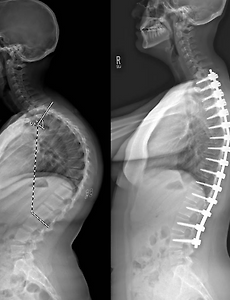

'척추 후만증(Kyphosis)' 척추 후만증(Kyphosis)은 척추가 정상 범위보다 과도하게 굽어 있는 상태를 말합니다. 이러한 척추의 변형은 노화, 선천적 요인, 질병, 또는 부상으로 인해 발생할 수 있으며, 심각한 경우 통증, 호흡 문제 및 신경학적 문제를 야기할 수 있습니다. 본 글에서는 척추 후만증의 정의, 원인, 증상, 진단 방법 및 치료 옵션에 대해 자세히 설명하고자 합니다. 척추 후만증의 정의 및 유형척추 후만증(Kyphosis)은 척추의 상부(흉추)가 정상보다 더 많이 앞으로 굽은 상태를 말합니다. 이 상태는 종종 "굽은 등" 또는 "거북목"으로 불리며, 척추의 정상적인 곡선이 50도 이상으로 증가한 경우를 지칭합니다. 척추 후만증은 크게 세 가지 유형으로 분류됩니다: 선천적 후만증(..

'척추 후만증(Kyphosis)' 척추 후만증(Kyphosis)은 척추가 정상 범위보다 과도하게 굽어 있는 상태를 말합니다. 이러한 척추의 변형은 노화, 선천적 요인, 질병, 또는 부상으로 인해 발생할 수 있으며, 심각한 경우 통증, 호흡 문제 및 신경학적 문제를 야기할 수 있습니다. 본 글에서는 척추 후만증의 정의, 원인, 증상, 진단 방법 및 치료 옵션에 대해 자세히 설명하고자 합니다. 척추 후만증의 정의 및 유형척추 후만증(Kyphosis)은 척추의 상부(흉추)가 정상보다 더 많이 앞으로 굽은 상태를 말합니다. 이 상태는 종종 "굽은 등" 또는 "거북목"으로 불리며, 척추의 정상적인 곡선이 50도 이상으로 증가한 경우를 지칭합니다. 척추 후만증은 크게 세 가지 유형으로 분류됩니다: 선천적 후만증(..